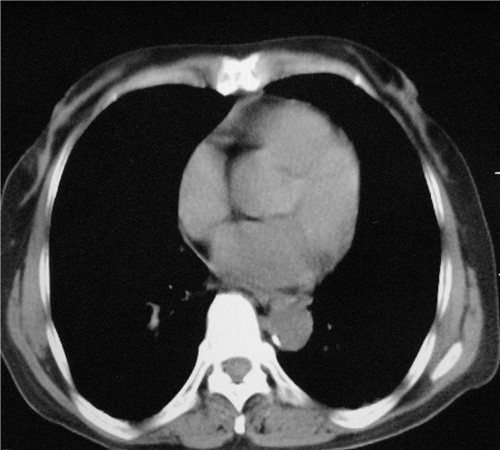

标题: CT26849:女67岁反复胸痛两天余,临床考虑夹层。 [打印本页]

标题: CT26849:女67岁反复胸痛两天余,临床考虑夹层。

右肺感染,未见夹层。

升主动脉增宽是怎么回事啊!食管有事吗?老师

既然考虑夹层,建议强化!另:右下肺感染!

1)右肺感染性病变。2)建议行ct增强扫描或mri检查排除主动脉夹层。

双下肺感染,右侧显著。有无夹层,增强扫描后再诊断。

1. 感染性病变,2.未见夹层,3.食道未见异常。

平扫未见确切夹层征,建议必要时增强扫描或mri检查。